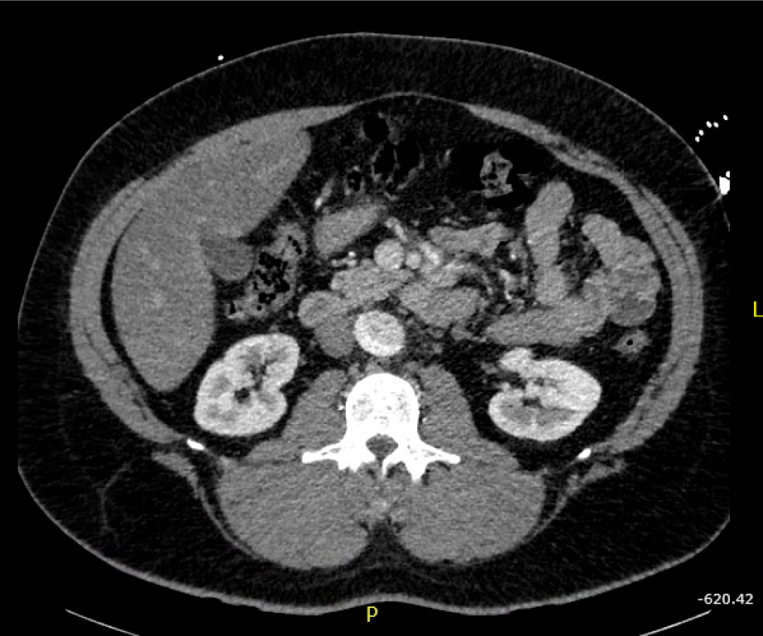

Patient’s initial EKG showed ST elevation in anterior leads, with possible ST depression in inferior leads, and T wave inversion in lateral leads. Given the patient’s clinical presentation and appearance, there was concern for ongoing ischemia. Based on the patient’s history of pain radiating into the abdomen and severe hypertension, there was additional concern for aortic dissection. This led to the cancelation of the catheterization lab activation. Slices of his computed tomography (CT) scan are shown below, revealing a severe type A aortic dissection, dissecting from the coronary arteries to the bilateral iliac arteries. Patient was started on nitroprusside and esmolol infusion and transferred emergently for cardiovascular surgery. He was discharged from the hospital in good condition less than one week later following an uncomplicated post-operative course.